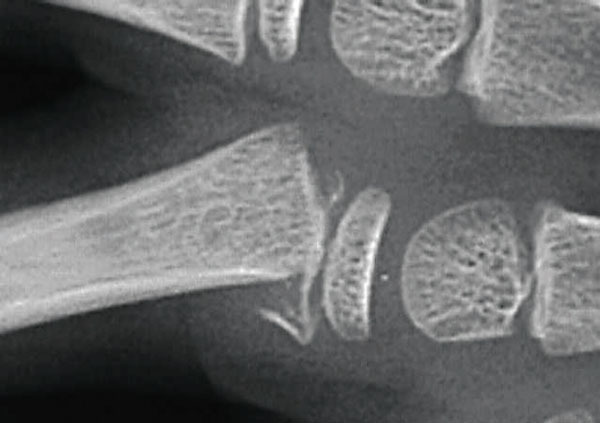

Fracture juxta-épiphysaire de la base de la première phalange.

Extrait de : Particularités des traumatismes de la main de l'enfant